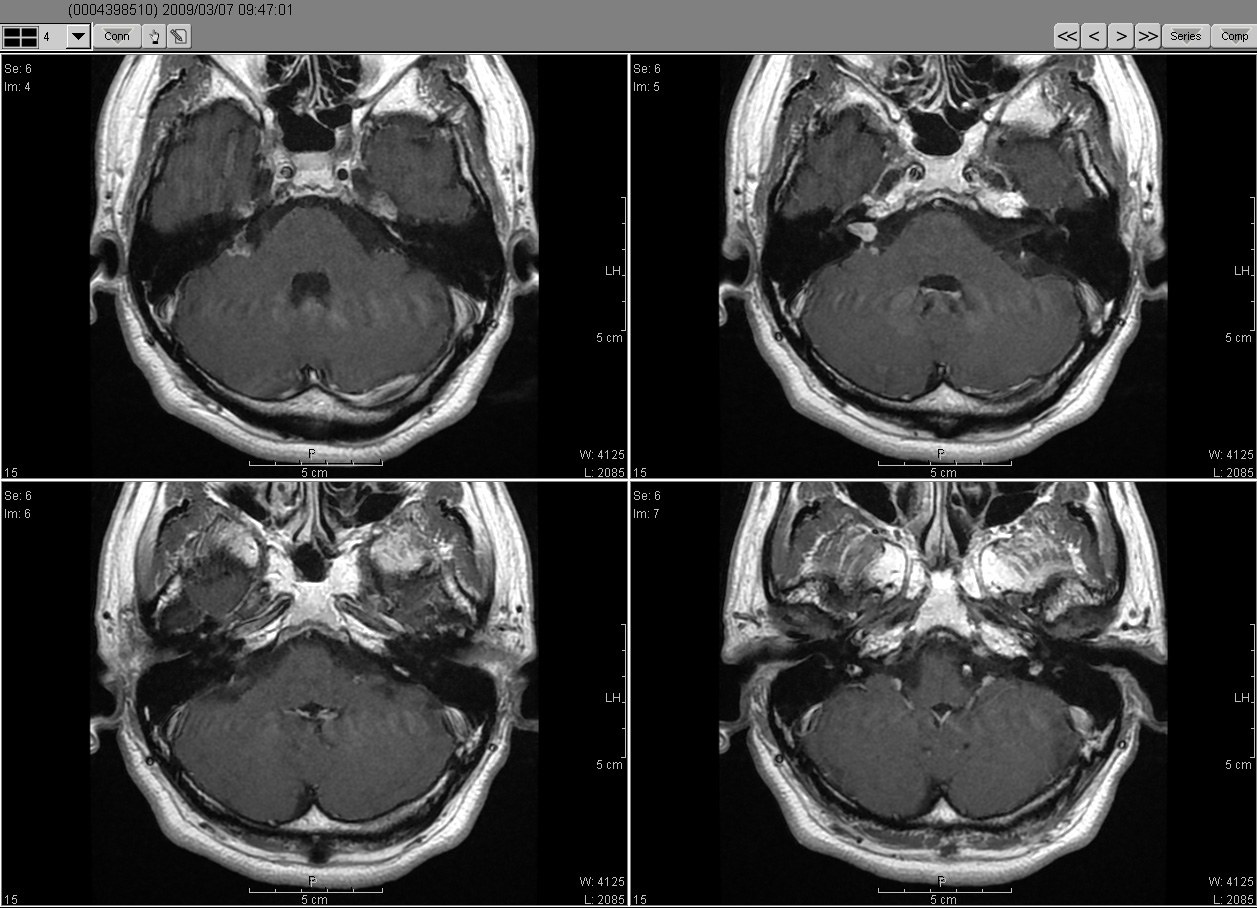

2009_03_07 MRI

2009_03_07MRI02